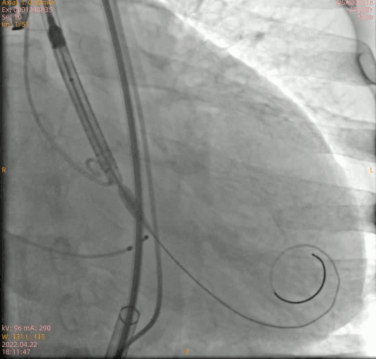

主动脉根部造影

预扩